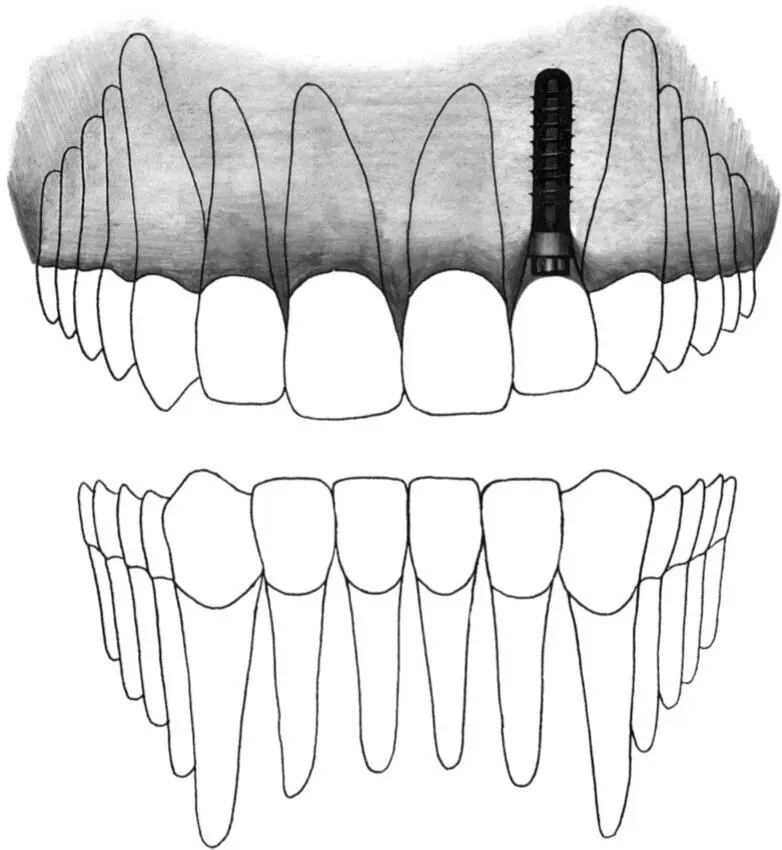

Fig 2-1 Standard implant.

Fig 2-1a Two standard implants are restored with a three-unit fixed partial denture in a mandibular distal extension situation. The implants provide adequate support and function against the opposing dentition.

Fig 2-1b For this single-tooth gap, a 12-mm-long standard implant is indicated to replace a missing mandibular second premolar.